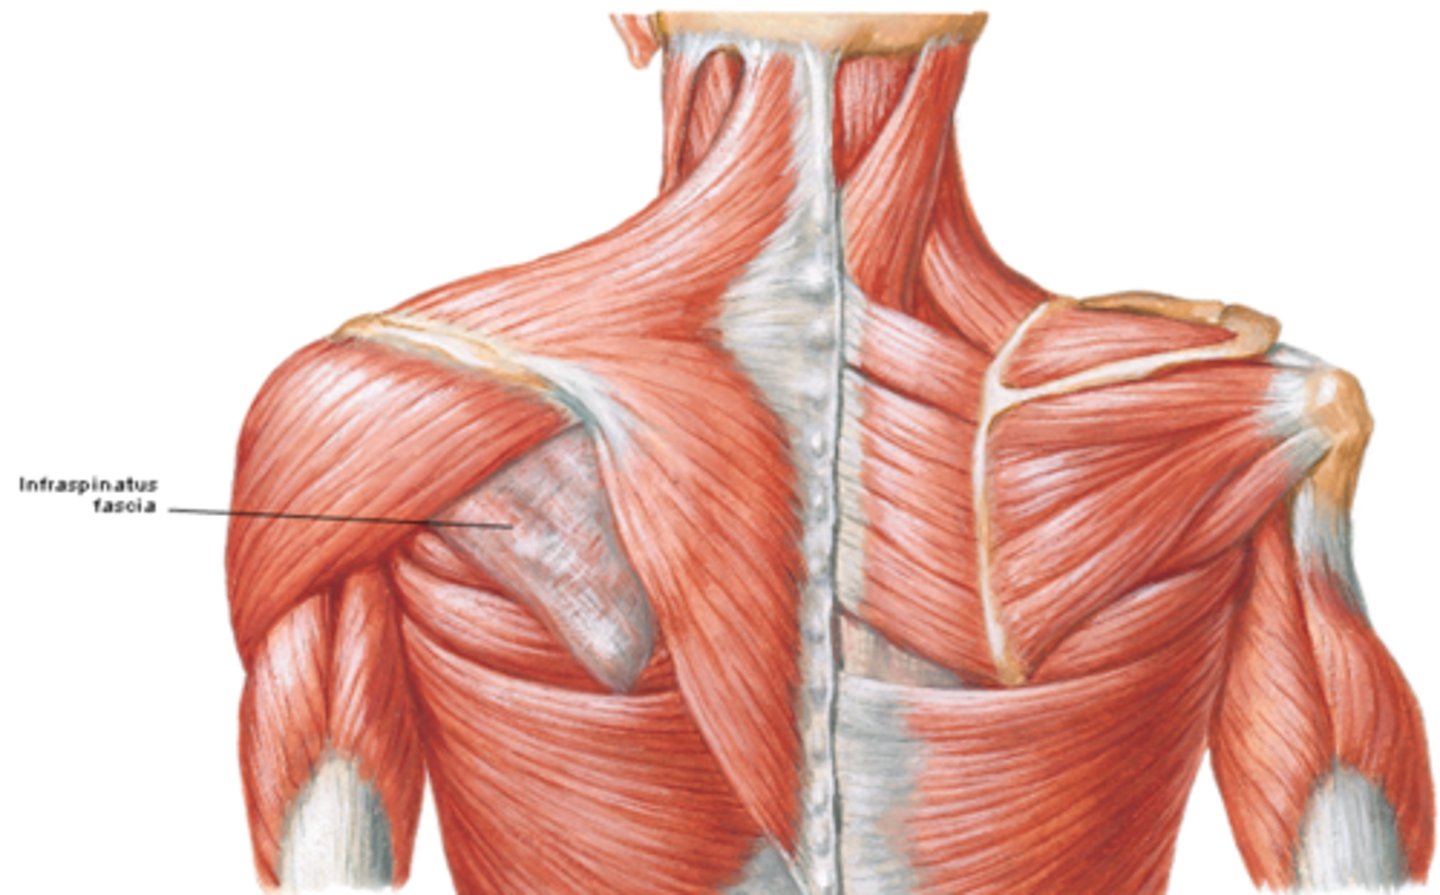

(Upper Limb Fascia:) Fascia of the shoulder region

•Deltoid fascia

•Supraspinous and infraspinous fascias

(Fascia of the shoulder region:) Deltoid fascia:

covers the deltoid muscle and is continuous anteriorly with the pectoral fascia and posteriorly with the infraspinous fascia

(Fascia of the shoulder region:) Supraspinous and infraspinous fascias:

overlies the supraspinatus and infraspinatus muscles, respectively; and attaches to the scapula

(Muscles of Pectoral region:) Posterior axioappendicular and scapulohumeral muscles

-These are superficial and intermediate back muscles and can be divided into:

*Superficial posterior axioappendicular muscles (extrinsic shoulder)

*Deep posterior axioappendicular muscles (extrinsic shoulder)

*Scapulohumeral muscles (intrinsic shoulder)

(Posterior axioappendicular and scapulohumeral muscles:) Superficial posterior axioappendicular muscles (extrinsic shoulder)

Trapezius and Latissimus dorsi

(Superficial posterior axioappendicular muscles (extrinsic shoulder):) Trapezius

-Elevates, depresses, and retracts scapula

-Accessory nerve (CN XI)

(Superficial posterior axioappendicular muscles (extrinsic shoulder):) Latissimus dorsi

-Extends, adducts, and medially rotates humerus

-Thoracodorsal n. (C6 - C8)

(Posterior axioappendicular and scapulohumeral muscles:) Deep posterior axioappendicular muscles (extrinsic shoulder)

Levator Scapulae and Rhomboid minor and major